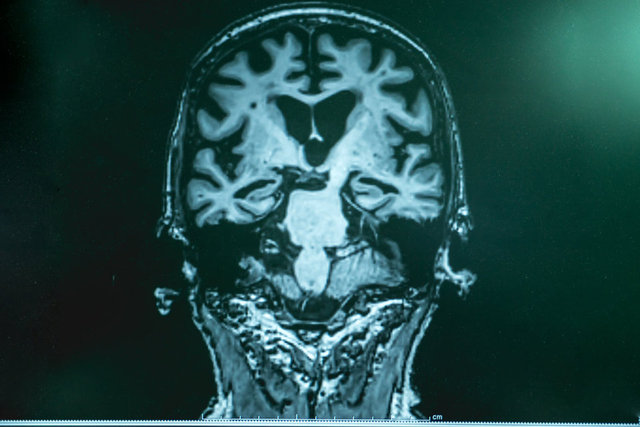

Her gün birkaç kare bitter çikolata yemekten, kendinize ait bir evcil hayvanınız yoksa komşunuzun köpeğini okşamaya kadar, beyninizin ilerleyen yaşlarda sorunsuz işlemesi için yapabileceğiniz şaşırtıcı derecede basit pek çok şey bulunuyor.

İngiliz Daily Mail'de yer alan habere göre, demansın en yaygın nedeni olan Alzheimer hastalığını tedavi etmek için yeni nesil ilaçları araştıran heyecan verici denemeler devam ediyor olsa da, bunların kullanımı henüz onaylanmadı ve ciddi yan etkileri olabilir.

Bu nedenle araştırmalar giderek daha fazla beynin ilk etapta bozulmasını önlemeye yardımcı olacak yollara odaklanmaktadır.

Yardım kuruluşu olan Alzheimer's Society'ye göre demans vakalarının yaklaşık yüzde 40'ı önlenebiliyor. İşte alanında önde gelen uzmanlar tarafından önerildiği üzere riskinizi azaltacak 19 yaşam tarzı değişikliği...